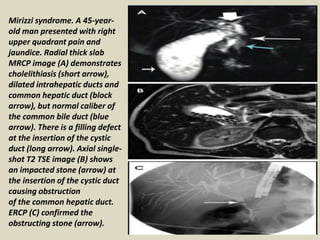

Mirizzi syndrome. A 45-year-

old man presented with right

upper quadrant pain and

jaundice. Radial thick slab

MRCP image (A) demonstrates

cholelithiasis (short arrow),

dilated intrahepatic ducts and

common hepatic duct (block

arrow), but normal caliber of

the common bile duct (blue

arrow). There is a filling defect

at the insertion of the cystic

duct (long arrow). Axial single-

shot T2 TSE image (B) shows

an impacted stone (arrow) at

the insertion of the cystic duct

causing obstruction

of the common hepatic duct.

ERCP (C) confirmed the

obstructing stone (arrow).